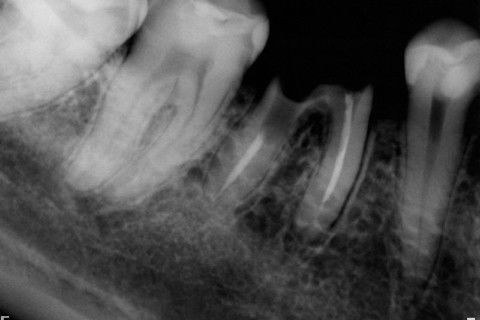

Retratamento de Canal, Tratamento de Perfuração, Restauração Provisória com Resina, Núcleo e Provisório.

RETRATAMENTO DE CANAL, TRATAMENTO DE PERFURAÇÃO, RESTAURAÇÃO PROVISÓRIA COM RESINA, NUCLEO E PROVISÓRIO.